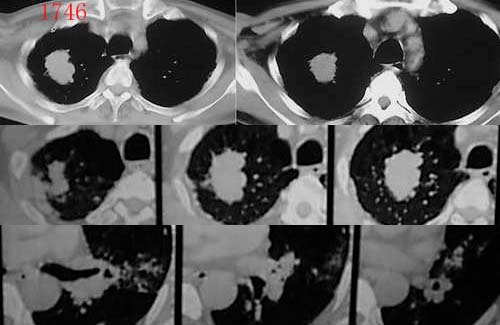

肺癌--腺癌

ct1746 pingfanjun提供 结果右上肺腺癌

76岁;咳嗽、咯血、气短、呼吸困难一年余

http://www.radida.com/radinet/read.php?tid=5255